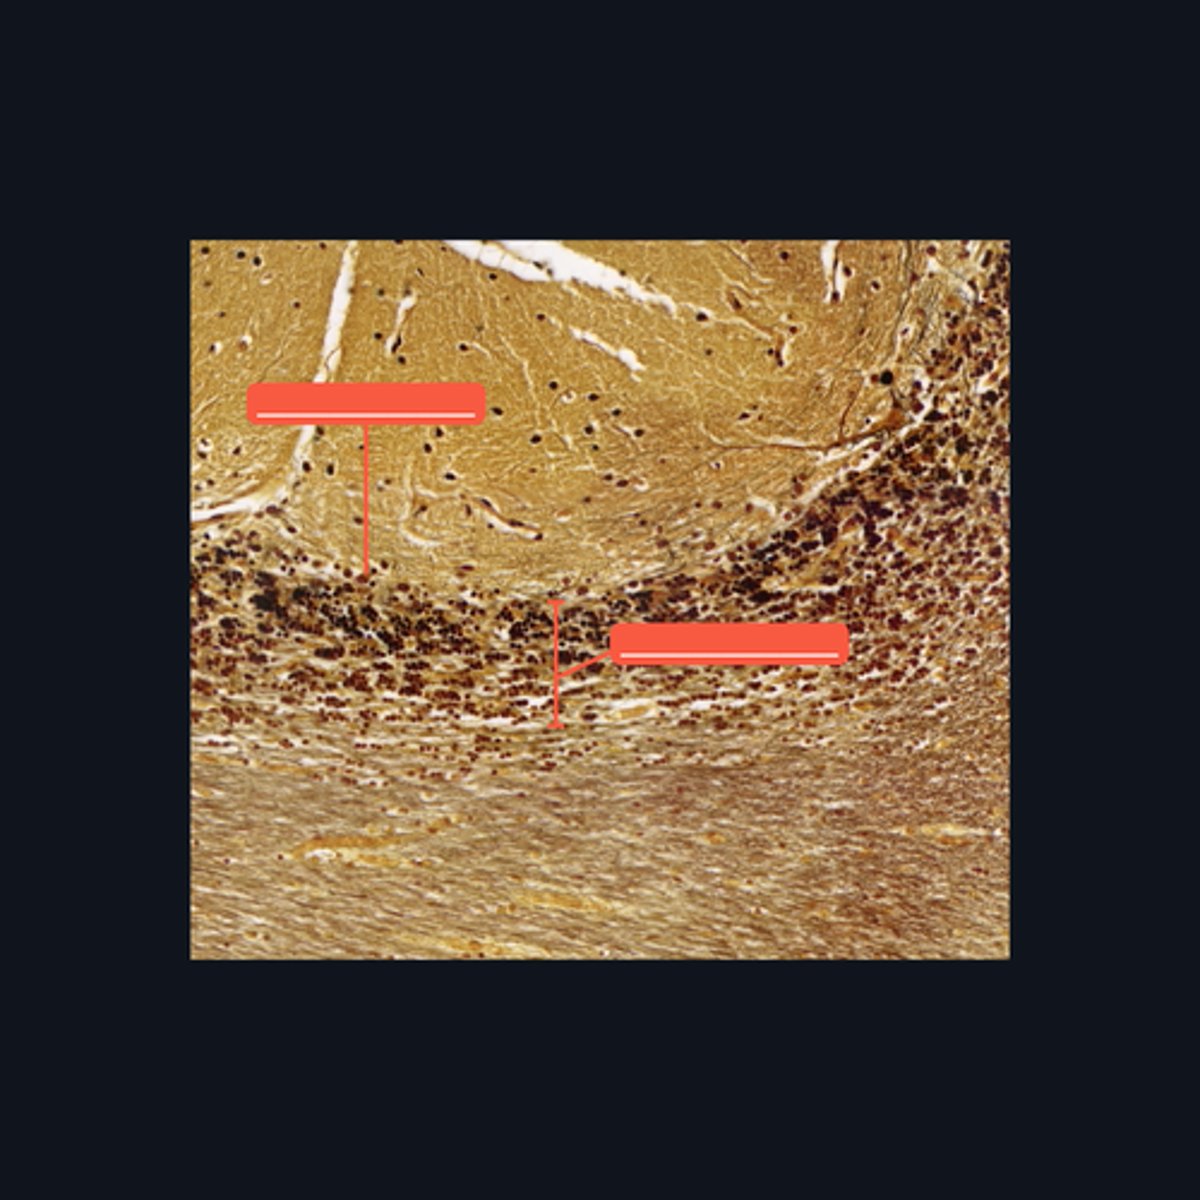

Gray Matter

Identify the pointed region in the spinal cord

(1) Ventral Horn, (2) Dorsal Horn

Identify the pointed regions of the gray matter of the spinal cord

Gray Matter (When looking at speciemen from the brain, all areas in the periphery are considered Gray Matter)

Identify the pointed region in the Cerebellum

"cell bodies, dendrites, proximal portions of the axons, and neuroglial cells"

Enumerate the structures found in the pointed region